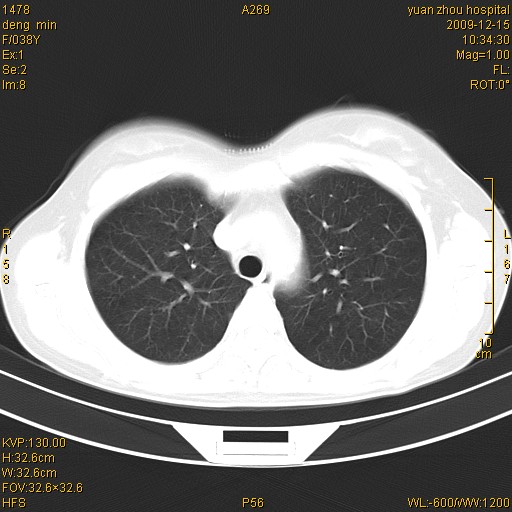

标题: CT23919:F38Y 咳嗽月余 [打印本页]

标题: CT23919:F38Y 咳嗽月余

右肺中下叶、左肺上叶舌段及左肺下叶支气管扩张合并感染。